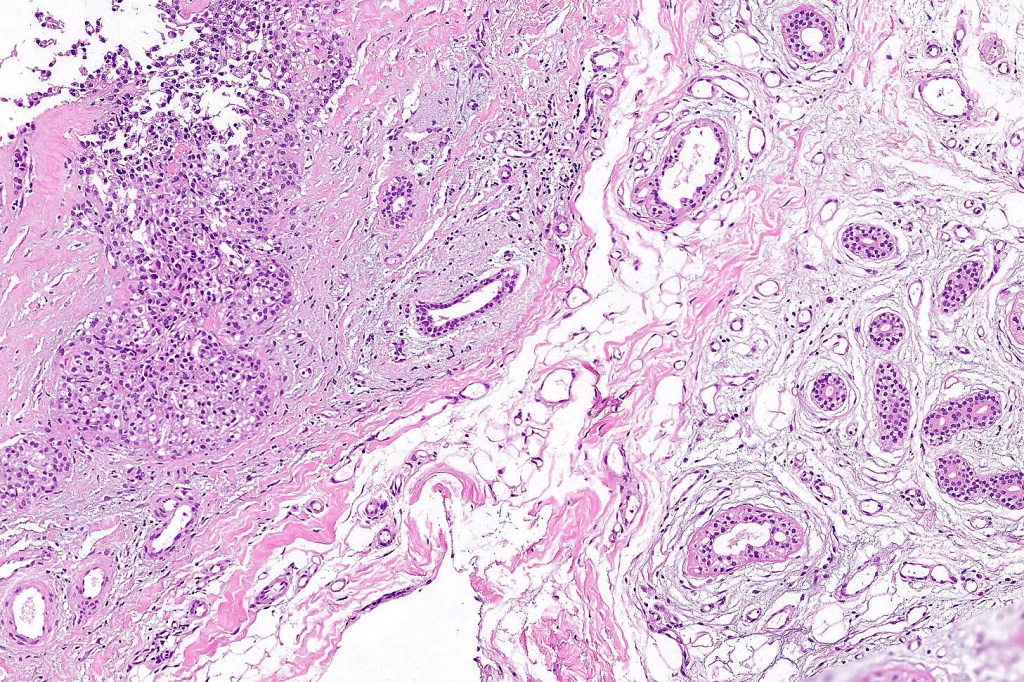

•Solid or cystic circumscribed or infiltrative dermal nodule

•Microcystic, tubular & solid patterns

•Vacuolated/granular/bubbly eosinophilic cytoplasm

•DPAS +ve luminal content

•Low grade atypia, mitoses very sparse, absence of perineural infiltration, lymphovascular invasion or necrosis